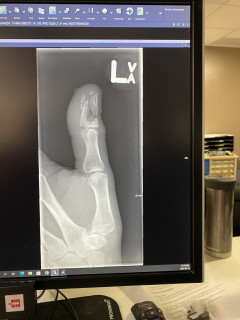

Mine doesn't look very bad, but it's quite deformed, nail out of the socket on a side, and skin burst on a side. Hoping for a miracle that the bone isn't crushed, but...

The dr is proud of me he said I did a good job of shattering it.

Oh wrll. Hurts good

OMG @Eugen you did a number on that . Hurt just looking at it . I have hit the wrong nail before , but never that bad . Are they able to fix it ? Hope they were able to give you something for the pain that doesn't leave you loopy . How did you not go into shock after doing that ?

Oh dude! I'm aching just looking at the x-rays... Hope they gave you something stronger than plain Tylenol for the pain - that's gotta throb...